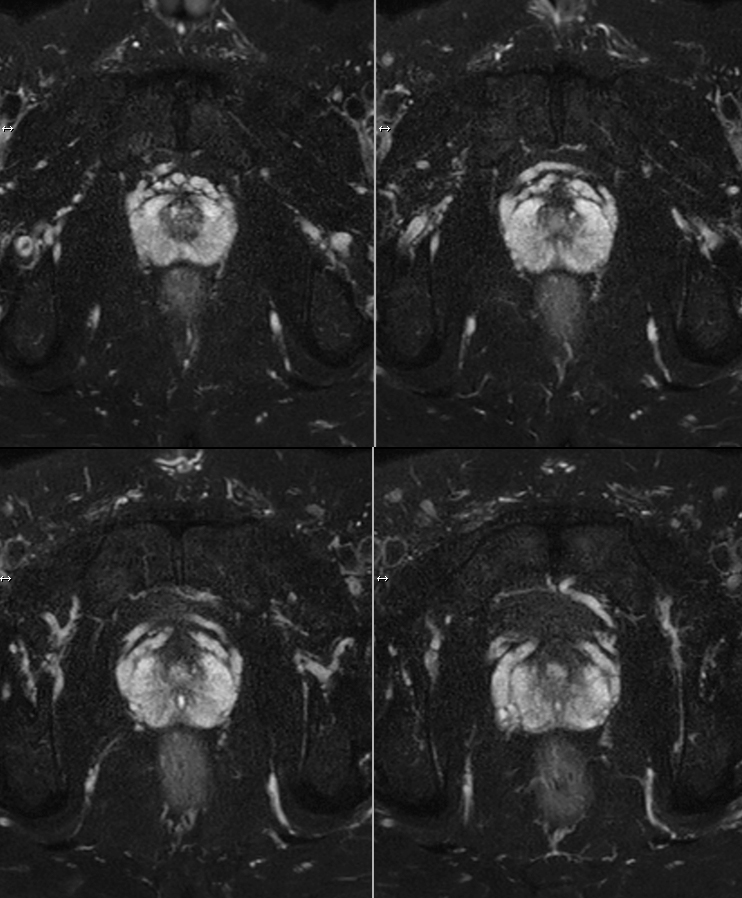

Prostate imaging

• Clinical Application